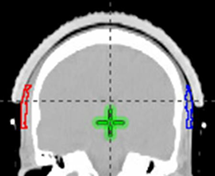

Figure 1F Template marks of repigmented hair were superimposed on the patient’s original planning scan. Red volume is right sided and blue volume is left sided. Axial slice.

Figure 1G Template marks of repigmented hair were superimposed on the patient’s original planning scan. Red volume is right sided and blue volume is left sided. Coronal slice.

Figure 1H Dose volume histograms (DVHs) were calculated for these volumes from the original dosimetry. Red line shows right repigmented hair dose characteristics. Blue line shows left repigmented hair dose characteristics.